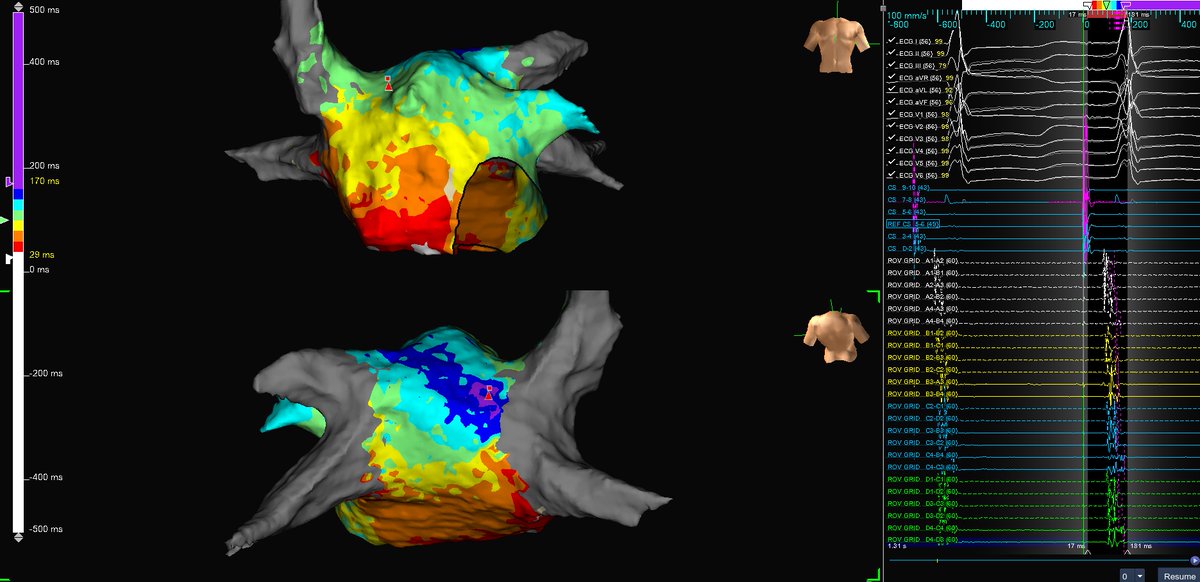

Micro-reentrant AT Mondays?!? Let's go! 🎯 Entire re-entrant circuit on the Grid EGMs imperceptible on recording system <0.06 mV Annotated automatically based on frequency w #OTNF One burn term 🔥🔥#MapMoreBurnLess @AbbottCardio

Entire re-entrant circuit on the Grid

EGMs imperceptible on recording system &amp;lt;0.06 mV

Annotated automatically based on frequency w #OTNF

One burn term 🔥🔥#MapMoreBurnLess